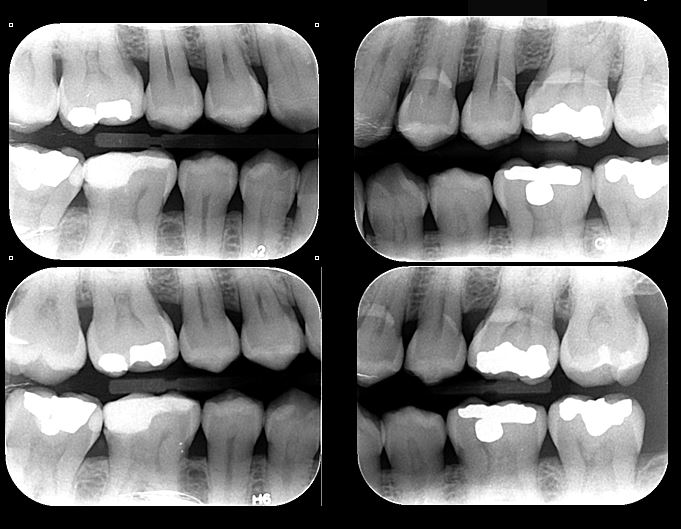

- Radiografías Bite-Wing: Radiografía que permite evaluar en detalle la corona de un diente con la finalidad de diagnosticar caries interproximales, desajuste de restauraciones, pérdida ósea y demás.

Se utilizan principalmente radiografías periapicales, Bite-Wing y oclusales, cada una con funciones específicas para evaluar diferentes estructuras y patologías en la cavidad oral.

Esta radiografía es útil para detectar caries interproximales, evaluar desajustes en restauraciones y valorar la pérdida ósea en los dientes.